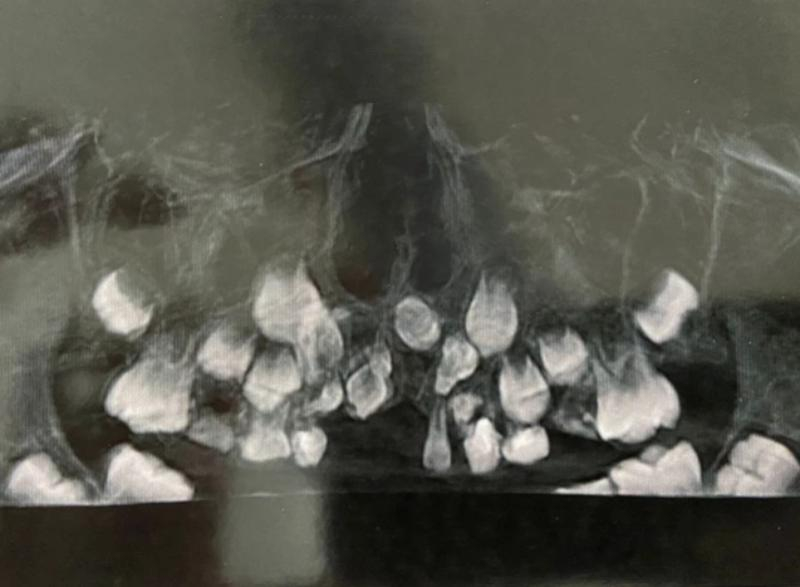

Редкая аномалия видна на снимке фото: Минздрав РО

В ходе осмотра врачи обнаружили, что в верхней челюсти мальчика расположены сверхкомплектные зубы необычной формы, расположенные хаотично. Они мешали обычным зубам развиваться, а ребенку нормально жить. Это, по словам медиков, крайне редкий случай, с которым они сталкивались редко. Вызван он вероятнее всего аномалией развития.

— Технически эту операцию не назвать сложной, хотя длилась она порядка полутора часов. Но фактически процедура весьма непростая. Сверхкомплектные зубы скрыты в кости. Их видно на снимке, но манипуляция в кости несет в себе определённые риски, — сообщил челюстно-лицевой хирург ОДКБ Сергей Карнута.